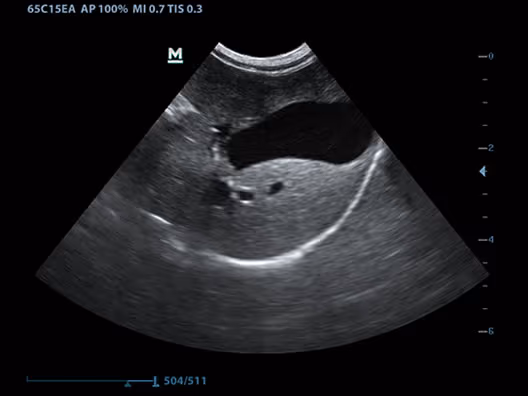

Safra Kesesi, Karaciğer, Köpek